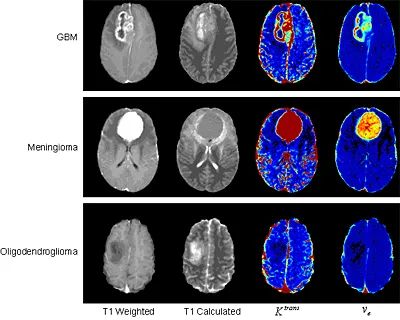

Permeability imaging (dynamic contrast-enhanced MRI) involves the repeated acquisition of T1-weighted MR images following injection of a contrast agent such as gadolinium. Overview Purpose Detail Contact Dr Michael Thrippleton Relevant links Brain & nervous system What is a MR scan? Multiple sclerosis (MS) Stroke Small vessel disease (SVD) In the brain, the method can show quantitative information about the integrity of the blood-brain barrier (BBB). The BBB separates the parenchyma of the central nervous system from the blood. It regulates the passage of essential molecules while restricting the diffusion of potentially harmful substances. Disruption of the BBB can enable the extravasation of contrast agent, leading to an accumulation of contrast material in the extravascular extracellular space (EES). This results in increased longitudinal relaxation rate and, therefore, increased signal intensity in T1-weighted images. DCE-MRI exploits this T1 enhancement in order to detect and evaluate regions of BBB disruption. The repeated acquisition of T1-weighted images provides measurements of signal enhancement as a function of time, which differ between healthy and pathologic tissue (see Figure 1). The enhancement kinetics can be used to extract information regarding BBB integrity. Different approaches have been used to analyze DCE-MRI data, ranging from relatively simple visual assessment of enhancement curves to more complex fitting of pharmacokinetic models. Pharmacokinetic modelling can be used to relate the measured concentration-time curves to underlying physiological parameters relating to the contrast agent leakage. Pharmacokinetic modelling in DCE-MRI typically measures parameters relating to the permeability (permeability-surface area PS) and the volume of extravascular extracellular space (ve) and blood plasma space (vp), although with higher temporal resolution acquisitions it is also possible to gain information on tissue perfusion (blood flow Fp). An important physiological parameter that is widely reported in DCE-MRI studies is the volume transfer constant KTrans, which is the rate at which contrast agent is delivered to the EES per volume of tissue and contrast agent concentration. Image Figure 1. Typical signal enhancement "leakage profiles" characteristic of different tissue types in the brain, whereby malignant tumour tissue shows a high and fast enhancement followed by washout, benign tissue demonstrates a more progressive enhancement and normal tissue shows very little enhancement. Research Typical applications for DCE-MRI involve clinical disorders resulting in disruption of the blood-brain barrier. The most common imaging applications are in the study of focal lesions such as brain tumours (see Figure 2), multiple sclerosis plaques and acute ischaemic strokes. While these diseases show relatively large abnormalities in BBB functionality, there is also growing interest in the application of DCE-MRI to pathologies associated with more subtle and chronic BBB disruption, such as diabetes, cerebral small vessel disease, lacunar stroke (see Figure 3) and Alzheimer’s disease. We are currently working with Anna Heye, a PhD student, whose project aims to improve the methodology of permeability imaging in small vessel disease and, thus, to move closer towards reliable quantification of subtle BBB abnormalities. Although there are many approaches for acquiring and analysing DCE-MRI data, these have mostly been developed for oncology applications, where vessel density and permeability are typically high. However, the optimal approach for detecting subtle BBB permeability is unclear. The small changes linked to subtle BBB breakdown are most likely influenced by secondary processes, such as random noise, scanner drift or partial volume effect. In order to enable reliable quantification of BBB integrity, it needs to be investigated whether the measured changes in the contrast-agent concentration curves are due to BBB disruption or other mechanisms. Furthermore, the project aims to find the most suitable approach for analysing DCE-MRI data related to subtle BBB disorders. Recent and ongoing projects utilising this methodology include: Studies of permeability, perfusion and diffusion changes following dexamethasone treatment in high-grade intracranial tumours. Investigation into the contrast leakage related to small vessel disease and lacunar strokes Identification of leakage pattern distributions in a series of Alzheimer's disease patients compared to normal matched control subjects. Measurement of permeability, and diffusion changes following radiotherapy treatment in low grade intracranial tumours. Image Figure 2. Example images obtained using DCE-MRI for three different types of intracranial tumour. Images shown are (from left to right) post-contrast T1-weighted, absolute T1, permeability-surface area product per unit volume of tissue (Ktrans) and extravascular extracellular space volume fraction (ve). The T1-weighted image is a standard clinical acquisition; the absolute T1 map gives a quantitative indication of tissue water content and is useful for assessing oedema; Ktrans indicates the endothelial permeability and ve shows the EES volume fraction, both of which provide an indication of blood-brain barrier integrity, which is clearly compromised more in the aggressive high grade tumours. Image Figure 3. Preliminary data from 14 lacunar and 7 cortical stroke patients showing concentration-time curves obtained from grey and white matter regions of interest, which provide evidence that there may be a difference between the contrast agent accumulation properties in these different stroke sub-types. Staff contact If you wish further information on the above activities, please contact Dr Michael Thrippleton: Dr Michael Thrippleton This article was published on 2024-08-22